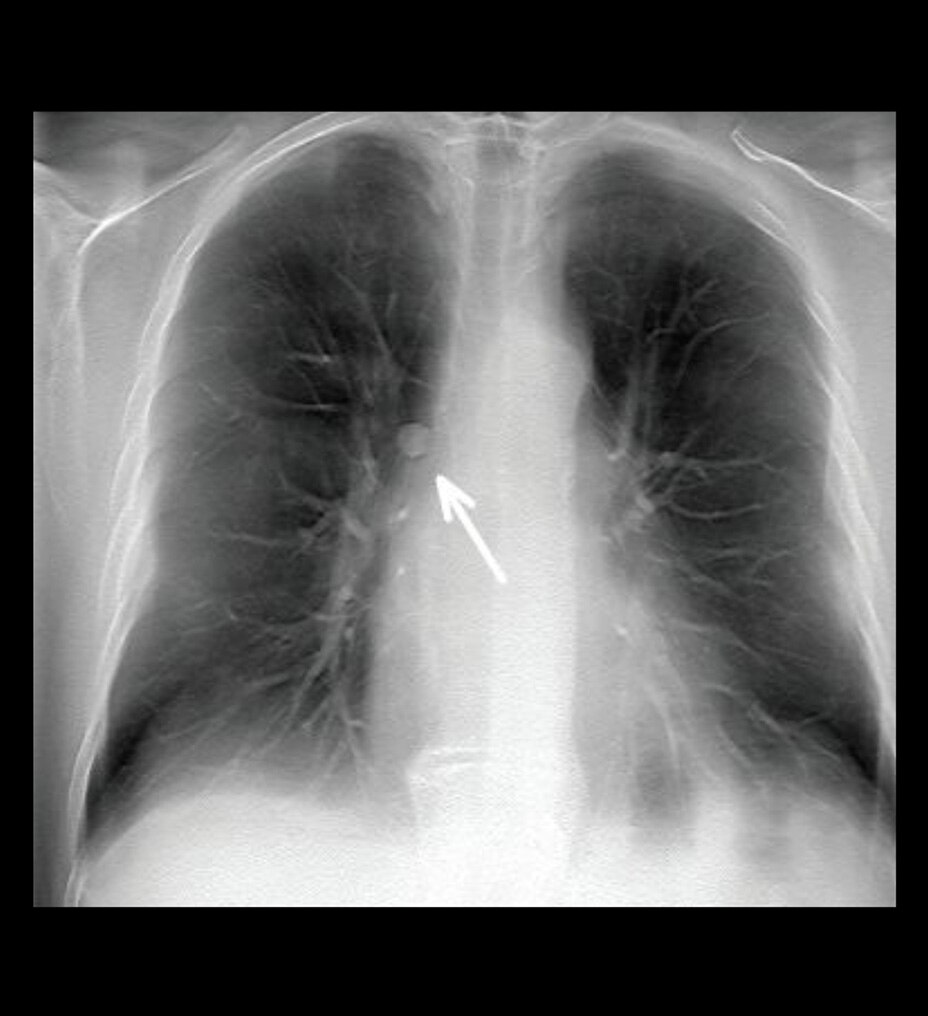

• Imagerie corporelle, y compris les seins et les reins

Très efficace en imagerie à l’état stable comme en imagerie dynamique 2-6,12

La haute relaxivité de Pixxoscan constitue un avantage pour l’amélioration des images à l'état stable3-6,12.

Par ailleurs, le bolus plus étroit du gadobutrol est conçu pour optimiser la visualisation lors de l’imagerie dynamique, offrant ainsi des avantages potentiels dans certains contextes cliniques2.